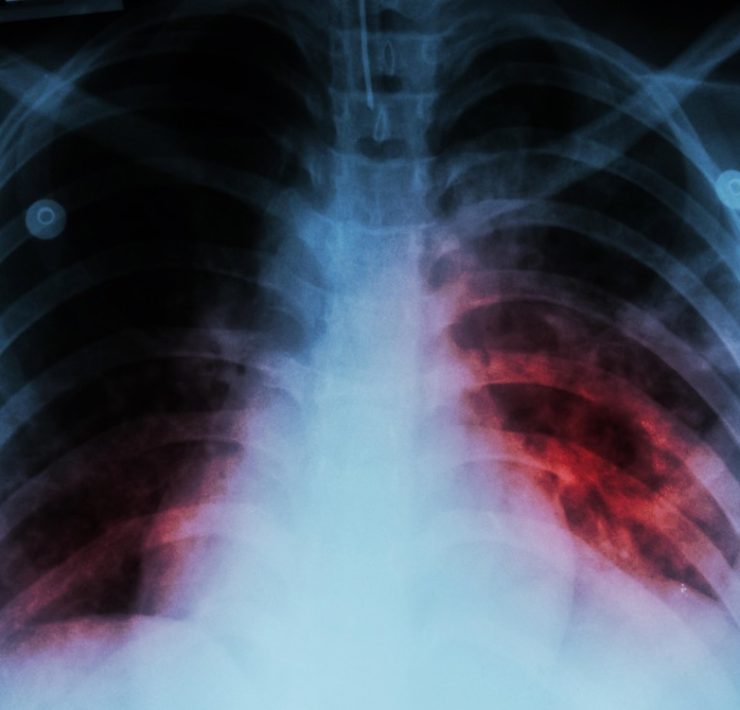

Ciudad del Carmen, Camp.__ Pocos casos de tuberculosis en el estado de Campeche; de acuerdo con la Secretaría de Salud a nivel nacional, en el 2022, se registraron 28 mil casos de tuberculosis (TB), por lo tanto en el estado de Campeche, es mínima la incidencia, La tuberculosis es una bacteria que suele afectar a los pulmones, se propaga por el aire cuando una persona infectada tose, estornuda o escupe, dijo el presidente de la Asociación de Médicos Egresados de la Universidad Veracruzana, AC, Froilán Palestino Cruz.

Expresó que el control que tiene esta enfermedad en el país, se debe a que dentro del esquema de vacunación de los recién nacidos se les aplica la vacuna que previene la tuberculosis. Si en algún momento al recién nacido no se le aplica la vacuna, puede presentar el cuadro de tuberculosis por la bacteria y se le puede producir un cuadro mayor.

La tuberculosis tiene tratamiento

Indicó que, la tuberculosis tiene tratamiento, pero si no se diagnostica a tiempo puede presentar hasta la muerte. Si tienes tuberculosis latente, el médico podría recomendarte un tratamiento con medicamentos si presentas riesgos altos de tener tuberculosis activa; para la tuberculosis activa el médico recomienda, tomar antibióticos por lo menos por seis a nueve meses.